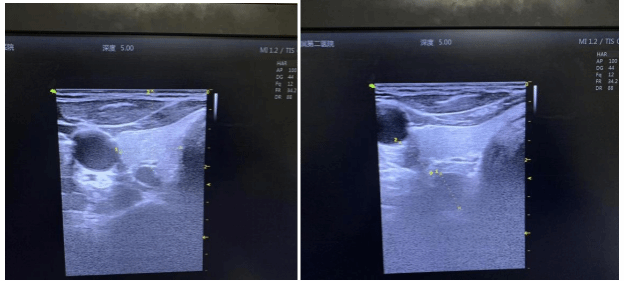

术前B超检查发现两个增大的甲状旁腺

韩某某,男,52岁,维持性血液透析12年,出现骨痛、皮肤瘙痒等表现,外院诊断继发性甲状旁腺功能亢进,使用“帕立骨化醇、西那卡塞”等药物抑制甲旁亢,效果不佳,甲状旁腺素逐渐升高,为求治疗慕名来到我院肾内科就诊。查PTH 165 pmol/ml,B超检查发现两个增大的甲状旁腺,邵阳学院附属第二医院肾内科及风湿免疫科主任王兴健立即组织甲状腺及乳腺外科、麻醉科、心血管内科等多学科进行联合会诊,对患者进行全面评估,决定采用微创手术--甲状旁腺腺射频消融治疗。